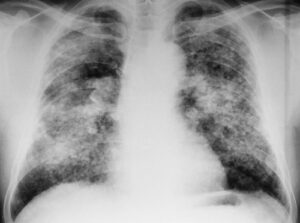

Снимки легких при туберкулезе

С момента открытия рентгеновских лучей (рентгеновских лучей) он активно внедряется во все области медицины, и фтизиология не является исключением. Поскольку легкие у больных туберкулезом имеют отличительные особенности, радиологические методы стали применяться для диагностики, наблюдения за динамикой процесса и профилактики. Перечень визуализационных методов исследования Для диагностики туберкулеза используются следующие анализы: флюорография; Рентгеновская радиография; компьютерная томография (КТ). …